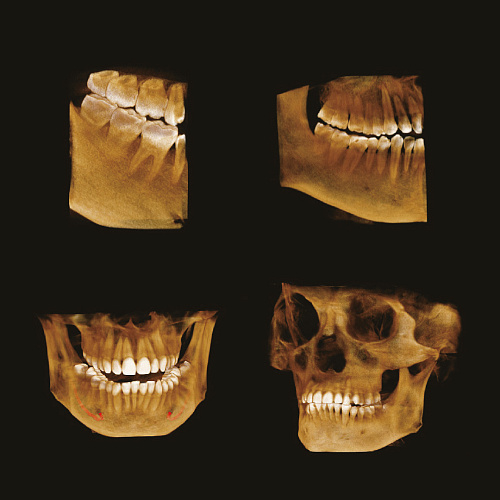

Пример 3D исследования дентального компьютерного 3D томографа Volux 55 Genoray.jpg

70 мкм в Эндодонтическом режиме 3,5×4 см

Высокотехнологичный детектор с самым высоким разрешением в классе – 70 мкм. Позволяет различить даже самые мелкие анатомические образования и облегчит постановку диагноза в сложных случаях. А вместе с применением алгоритма SMARF инородные тела из металла не испортят качество снимков.